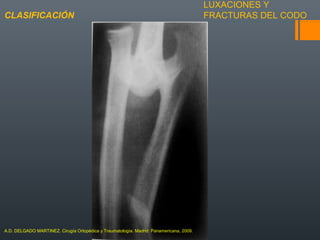

LAS FRACTURAS DEL HÚMERO DISTAL SON

AQUELLAS COMPRENDIDAS DENTRO DEL

CUADRADO DE HEINZ

INCIDENCIA BAJA EN LOS ADULTOS (0.5% DE

TODAS LAS FRACTURAS

FRACTURAS DE HÚMERO

DISTALGENERALIDADES

A.D. DELGADO MARTINEZ. Cirugía Ortopédica y Traumatología. Madrid: Panamericana, 2009.